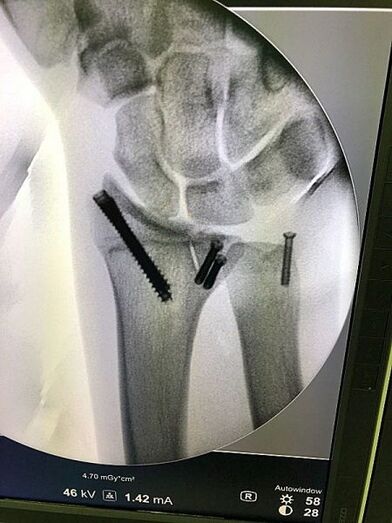

El prestigioso doctor Xavier Mir, traumatólogo y cirujano ortopédico especialista en microcirugía de la mano ha sido quién ha operado a Joan Barreda de una fractura borde cubital del radio distal derecho sin consolidación y de una fractura desplazada de la estilodes cubital de la misma muñeca izquierda, en ambos casos se ha procedido a una reducción abierta y una fijación interna mediante tornillos canulados a compresión.

La operación tuvo lugar el pasado jueves 15 de febrero en la Clínica Dexeus de Barcelona y, según el doctor Mir, tras permanecer inmovilizado durante dos semanas, el piloto podrá iniciar la recuperación y rehabilitación a partir de la tercera semana.